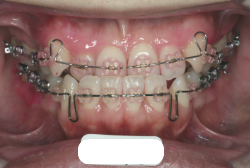

「乳歯が生え替わらない」という主訴で来院したケースです。 診断の結果、「左上永久犬歯が第一小臼歯後方上部に埋伏しているため、左上乳犬歯が晩期残存している症例」と判明しました。

このような症状の場合は、手術で埋伏している永久歯に金具を取り付け、矯正装置で牽引する必要があります。同時に凸凹の解消と前突した前歯を内側に入れるために上下左右の小臼歯を抜歯させて頂くことといたしました。

この方の場合は、マルチブラケット装置にて治療を開始し、治療期間2年3ヶ月で終了しました。犬歯の牽引距離が非常に大きかったため当院の平均治療期間よりも大幅に期間がかかりましたが、埋伏犬歯を完全に正しい位置まで誘導することができました。同時に 前歯の前突と配列の凸凹も解消しました。

マルチブラケット装置は、装置装着時より数日から2週間程度強い不快感疼痛が有りますが、本症例場合は埋伏歯を開窓手術し、遠く離れた位置に矯正器具が付いていますので強い違和感が生じ、歯ブラシも届きにくく口腔衛生状態を保つのにはかなりの努力が必要です。条件の悪い場所に接着されているため、装置が外れやすく日常生活上もかなり配慮が必要となります。

また、埋伏歯は移動距離が大きくなることが多く、歯根吸収のリスクが高まりますので、移動と休止にゆとりのある治療間隔が必要です。